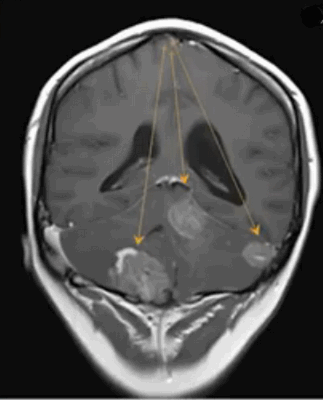

Метастазы в головном мозге на постконтрастном изображении (указаны стрелками)